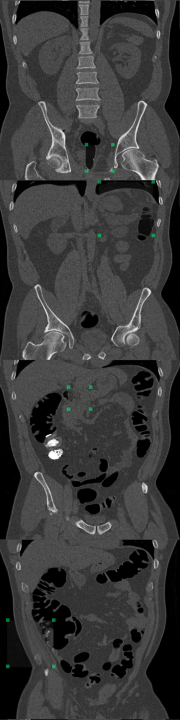

DeepLesion Dataset (Yan et al. (2018a)): this dataset contains CT scans from 4,427 unique patients exhibiting a broad range of lesions. There are at least eight different types of lesions including lung, abdomen, mediastinum, liver, pelvis, soft tissue, kidney, and bone. Each lesion is annotated with a bounding box. This dataset also includes volumetric data with slices above and below the annotated slice, typically about 30mm on both sides. In many cases, there are multiple annotated slices contained within one volume. To extract normal data from these volumes, we remove all annotated slices along with a margin about 10mm on either side. We train on 270,561 normal slices and test on 116,026 normal slices and 4831 annotated slices with lesions. A supervised benchmark is also trained using 22,496 slices with lesions and corresponding bounding box labels. Image-level testing uses normal slices and slices containing lesions. However, for pixel-level evaluation we only use slices with lesions. In this case, pixels inside bounding boxes are considered anomalous and all pixels outside of the bounding boxes are considered normal. All images are resized to 256x256. Performance is evaluated using AUROC and . Receiver operating characteristic (ROC) curves are also plotted.

At the image level, the reconstruction-based methods score around 0.5 or below. Several factors contribute toward this, including high variation in normal data, higher reconstruction error from certain structures, and overrepresentation of certain tissue types in the normal test data. Figure 8 shows that reconstruction-based models must learn to reproduce a wide range of structures and different organs. Most of the reconstruction error comes from sharp edges with high contrast and high spatial frequency, i.e., tissue interfaces. Also, the more pixels involved, the higher the contribution to the overall (image-level) anomaly score. As an example, the lungs generally have a high reconstruction error because they span across a large area and contain details with high spatial frequency. The lungs may also be overrepresented in the normal test data. As described in Section 3.1, each anomalous test image is accompanied by parallel slices that give context above and below the anomalous slice. The context slices, minus a margin around the anomalous slice, are used as normal test data, resulting in 116,026 normal test images and 4831 anomalous test images. However, certain regions have more context slices than others. For example, the average number of context slices for an anomalous lung image is 79, whereas soft tissue type lesions (muscle, skin, fat) only have 37 context slices on average. As such, the normal test data may be skewed toward certain organs that have high reconstruction error. This can increase the false positive rate and reduce the area under the ROC curve. This skew may exist in the training data as well, but reproducing details with high spatial frequency can still be challenging for methods that rely on a lower dimensional representation of the data.

Figure 9 displays anomalous examples from the DeepLesion dataset with bounding box labels for each lesion. The outputs from each method show varying levels of sensitivity. MMD-VAE exhibits reconstruction errors throughout the images which reflects the difficulty of learning a compact representation for data with high variation and detail. VQ-VAE2 uses a hierarchical architecture to produce higher fidelity reconstructions with less error. However, this does not help the network to be sensitive to specific irregularities such as lesions. Using the VQ-VAE2 for image restoration can help to highlight regions based on likelihood, rather than purely on intensity differences. This approach can be more selective, but it also tends to highlight certain natural variations that may be deemed less likely. Meanwhile, StyleGAN searches for a normal matching image in its latent space, but it is not always possible to find a good match when the data has complex and detailed structures that can vary greatly across images. In comparison to the reconstruction-based methods, FPI highlights more specific areas in the image that contain lesions or other unusual elements that are not lesions. Finally, the supervised method gives the most lesion-specific activations which can only be learned through labelled examples.